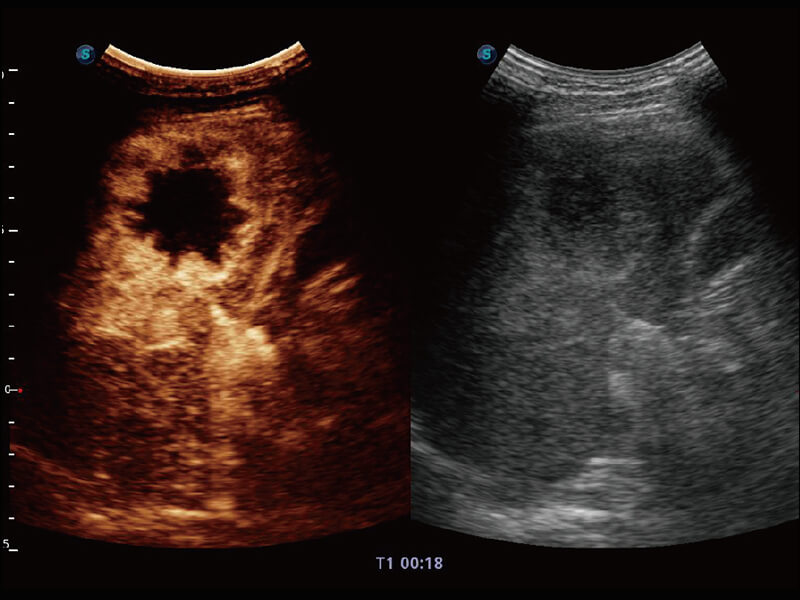

性能优异的硬件架构,极大提升超声系统的运行效率和数据处理能力。相比以往超声成像系统,Wis+平台为您带来极快的响应速度和成像帧频,提升检查流畅度。

S60探头工艺,从前端信号处理每一个环节采集无损声学数据,真实还原组织原貌,再现解剖细节。